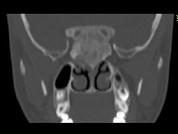

问题 女,17岁,鼻阻塞、头痛两年.如图所示符合筛骨病变最可能的诊断是 ( )

选项 A、骨瘤 B、骨化性纤维瘤 C、纤维异常增殖症 D、软骨瘤 E、成骨肉瘤

答案 B